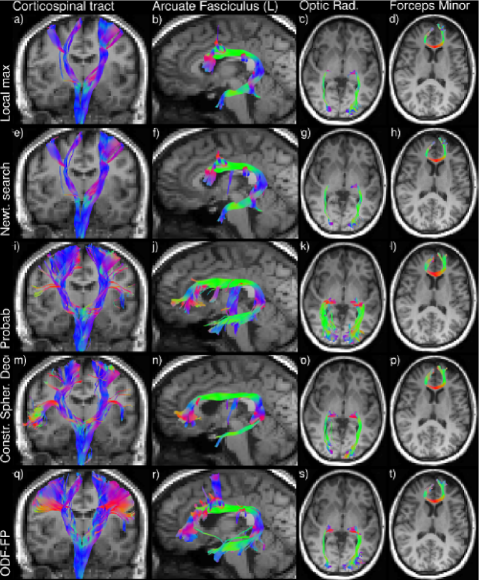

Refer to caption

Figure 11: Fiber tractography of the corticospinal tracts (a,e,i,m,q), the left arcuate fasciculus (b,f,j,n,r), the optic radiations (c,g,k,o,s) and the forceps minor (d,h,l,p,t) in a whole brain RDSI dataset. Fiber directions are identified by local maximum search (DSIStudio, a-d), Newton search (MRtrix3, shpeaks, e-h), probabilistic estimation (FSL, bedpostx, i-l), constrained spherical deconvolution (MRtrix3, dwi2fod msmt_csd, m-p) and ODF-Fingerprinting (ODF-FP, q-t).

Fiber tractography on a whole brain in vivo dataset shows that the fiber directions identified by ODF-FP (Fig. 10) allow the algorithm to improve results (Fig. 11). Fiber bundles generated with ODF-FP input probe the expected anatomical extent of the tracts in contrast to the fiber bundles based on ODF maximum search methods and CSD, in particular for the Corticospinal tract. The tendency of probabilistic methods to derive erroneous fiber directions (e.g. Fig. 6, ODF 1,4) produces more spurious tracts (Corticospinal tract, Arcuate Fasciculus and Optic Radiation in particular).

The application of key concepts from fingerprinting to the ODF based fiber direction identification task (Fig. 1e) improves the detection of fiber pairs crossing at small angles as shown in simulation results (Fig. 2,4). This is achieved while maintaining angular precision of fiber directions over the whole range of crossing angles (Fig. 5a,b,c S2d,e,f). In vivo bootstrap analysis shows that ODF-FP detects crossing fiber pairs where anatomically expected (Fig. 9) while not over-identifying fiber bundles in areas where no fiber bundles are expected such as in the CSF (Fig. 9, # fibers). Furthermore, the fiber directions identified with ODF-FP are reproducible over the bootstrapped datasets (Fig. 9, CI and κ𝜅\kappa) and reproduce the internal reference of an in vivo multi-resolution HCP dataset (Fig. 7-8). Consequently, the improved fiber detection results in increased adherence of fiber tractography to the underlying simulated microstructure (Fig. 3). Although no gold standard is available for in vivo tractography, the data suggest that the fingerprinting based method to improve tractography results (Fig. 10, 11).

Tractography algorithms guided by the more accurate fiber detection of ODF-FP adhere better to the underlying tissue microstructure (Fig. 11), thus enhancing the utility of tractography representations in clinical and neuroscientific applications. In neurosurgery, precise fiber bundle delineation informs surgical decisions (Fernandez-Miranda et al., 2012; Shin et al., 2012), while structural brain connectivity analysis is leveraged in neuroscientific research (Jbabdi et al., 2015; Galantucci et al., 2016; Mitra et al., 2016). Improved tractography will thus aid these endeavors.